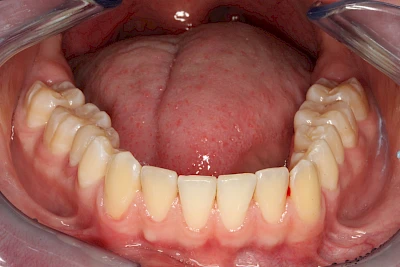

Verfärbungen an Zähnen können außen aufgelagert oder im Zahn eingelagert sein.

Von außen (exogen) eher dunkel gefärbt und meist mehrere Zähne betroffen:

Äußere Verfärbungen durch Genußmittel oder Medikamente (Eisen!) lassen sich meist nur durch den Zahnarzt z. B. mit einer professionellen Zahnreinigung entfernen.